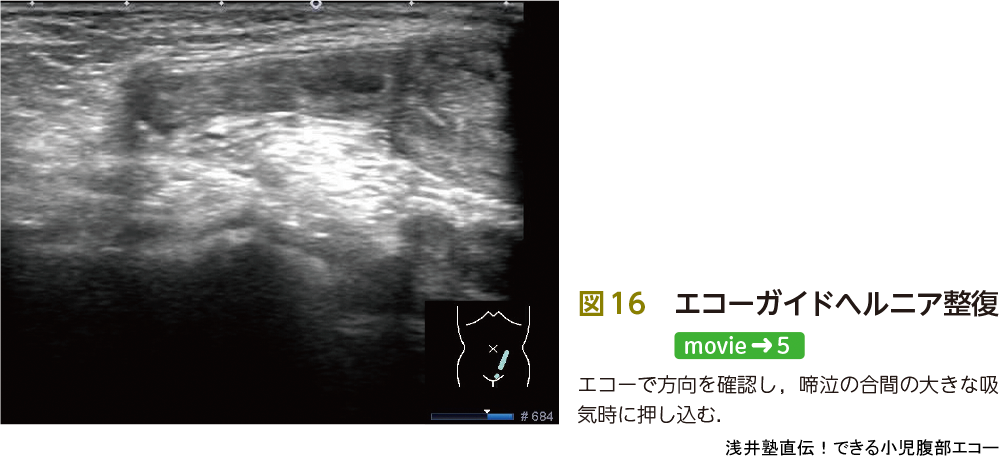

診断だけでなく,整復に関してもエコーが有用です.徒手整復の方法として,まず右手の手指でヘルニア内容を包み込みできるだけやさしく押し込みます.このときに左手が重要な役割を担います.拇指と示指を外鼠径輪に固定し整復方向をガイドします.私はこの左手のガイドをエコーガイドにしたらより効率よく整復できるのではないかと考えました(図15).

図16は6カ月男児の鼠径ヘルニア嵌頓です.この症例でどのように整復を進めたかについて説明します.整復不可能でエコーの依頼がありました.不可能と聞いても,慌てずにエコーです.抱っこしたままでも構いません.エコーで診断,内容物の確認をしたあとに画像のようにヘルニア門を同定します.どの深さに? どの角度に? と考えながら押し込んでいきます.過度の圧迫をかけると児は疼痛でもっと大泣き,大暴れです.そして間違った方向に押し込むと腸管はもっと浮腫性変化を起こします.この症例ではエコーガイドにより,整復に成功しました.